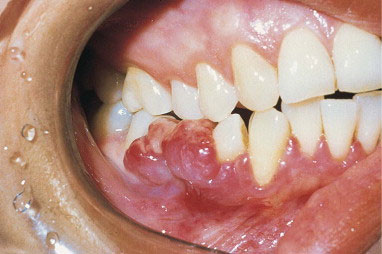

A reactive overgrowth of exuberant granulation tissue possibly in response to local irritation or trauma. This vascular mass often is ulcerated and may be smooth or lobulated and pedunculated or sessile.